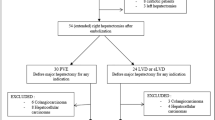

Over a 4-month period, seven non-cirrhotic consecutive patients (three women, four men; mean age: 63.6 years; range: 42–77 years) referred to our centres (University hospitals of Montpellier and Nice, France) for major hepatectomy in a context of small FRL, were included in this series (Supplemental Material 1). In each centre, the therapeutic strategy regarding these patients was discussed at our weekly tumours board meeting, including liver surgeons, oncologists, hepatologists and interventional radiologists. Tumours board meetings considered FRL as small when baseline FRL was <35 % of the total liver volume in patients with a suspicion of impaired liver function (bile duct obstruction [drained or not], multiple lines of oxaliplatin-based chemotherapy) and <30 % in the others. LVD was planned in all of these patients to increase FRL volume.